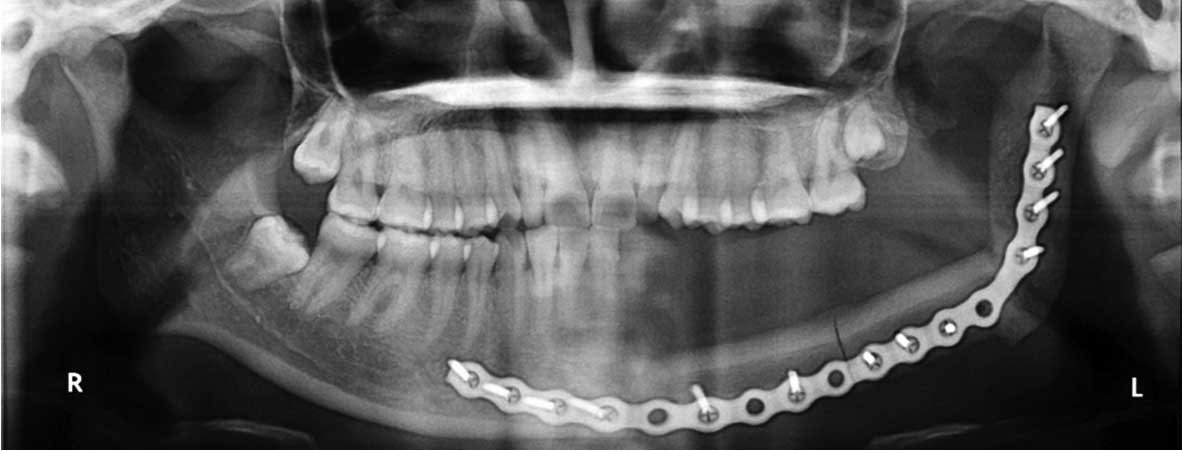

Рентгенологическая диагностика саркомы у кошек

Раздел: Визуальный дайджест